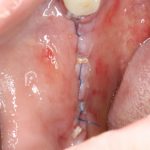

Если на этапе разреза и формирования раны всё сделано правильно, то наложение швов не вызывает особых трудностей. Периостотомия или послабляющие разрезы на периосте не требуются (ни практически никогда не требуются). А сами швы получаются аккуратными и герметичными:

Обрати внимание, что все шовные лигатуры находятся в пределах кератинизированной десны. Это позволяет избежать деформации тканей и лишних рубцов. В наиболее уязвимых местах (около зубов) шовные лигатуры лучше продублировать.

Если бы мне пришлось делать это сейчас, то я бы использовал непрерывный «матрацный» шов. Он удобнее, быстрее в наложении и комфортнее для пациента. Минус — если распускается, то распускается весь. К тому же, его очень неудобно снимать.

Несмотря на то, что уже тогда мы широко использовали непрерывные швы в подобных случаях, здесь я, во-первых, зассал (может распуститься), во-вторых, снятие швов предполагалось в поликлинике по месту жительства пациентки, и мне не хотелось, чтобы там при снятии швов начудили. Как выяснится позже — зря беспокоился.

Неизменно одно — в таких операциях мы использовали и до сих пор используем нерезорбируемые монофиламентные шовные материалы, поскольку они наиболее гигиеничные. Чтобы острые концы нитей не беспокоили пациента, их можно оплавить нагретой гладилкой или гуттаперчевым плаггером.